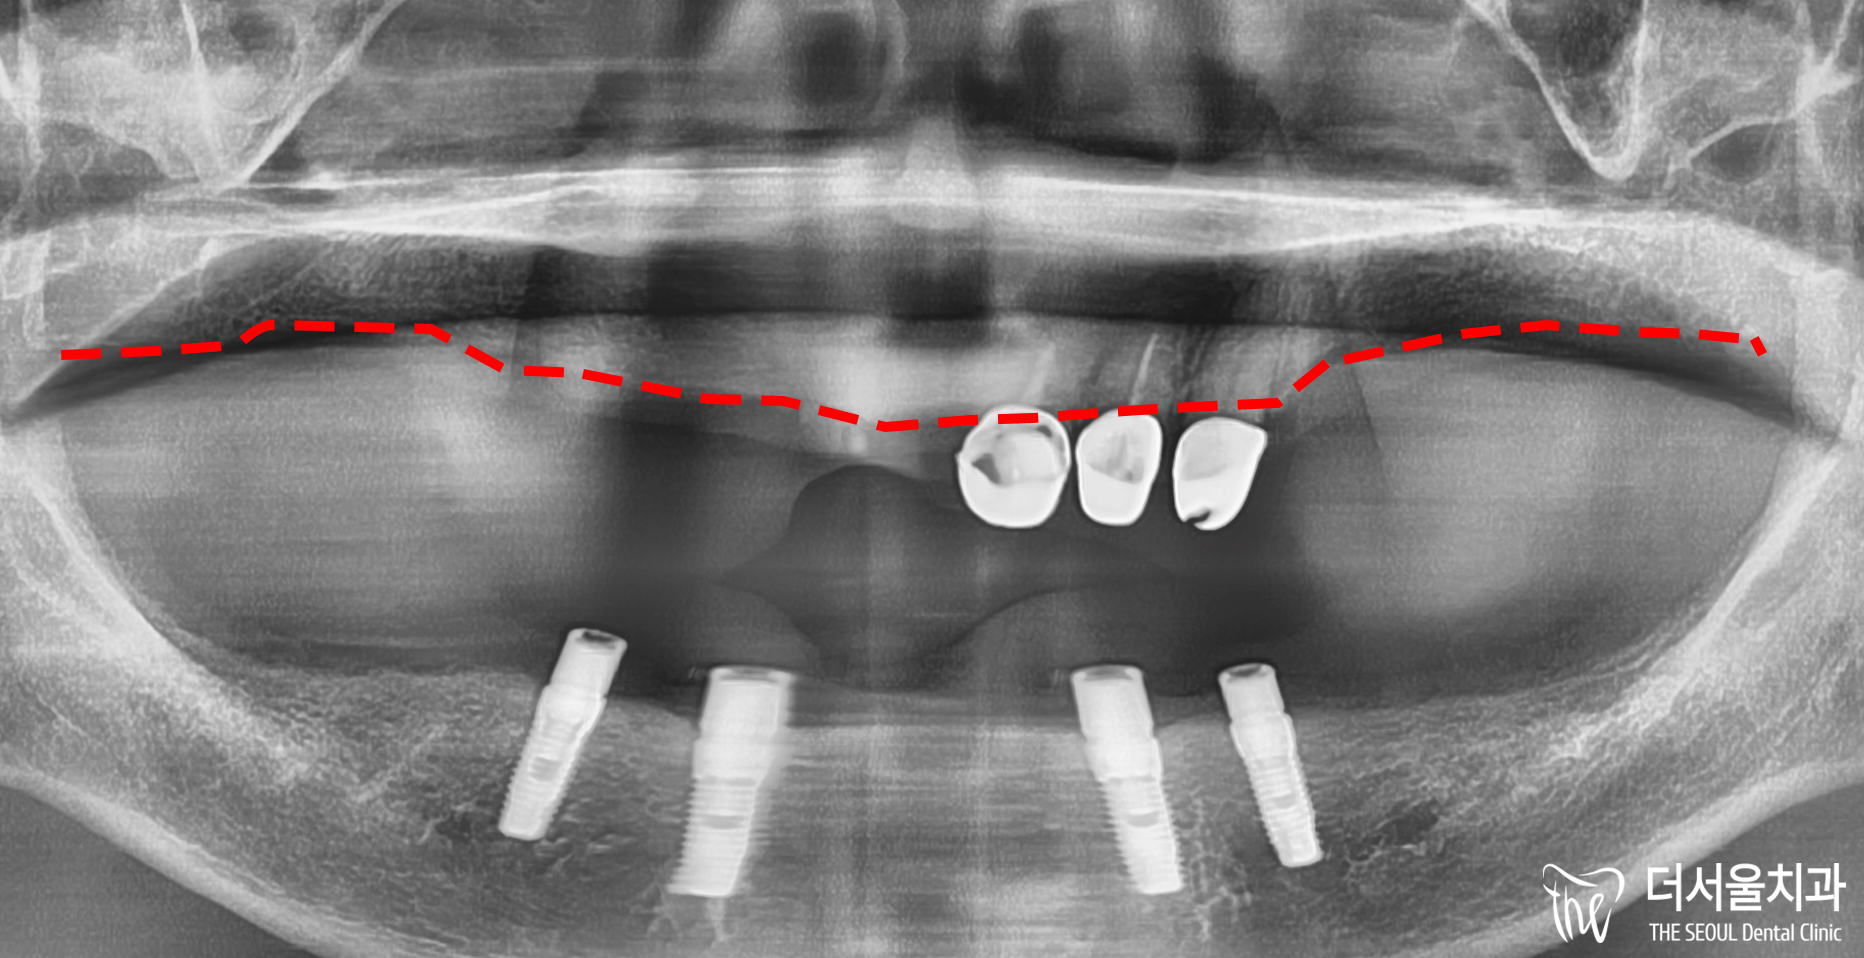

사진을 보면 잇몸뼈가 거의 없습니다.

자세히 보면 움푹 패어있어

뼈이식을 피할 수 없었는데요.

먼저 뼈가 두꺼운 곳을 찾아서

위치를 선정한 뒤에

부족한 부분은 뼈이식을 진행하기로 합니다.

엑스레이로 잇몸에 남아있는 뼈를 체크한 결과,

그렇게 좋은 상태는 아니었습니다.